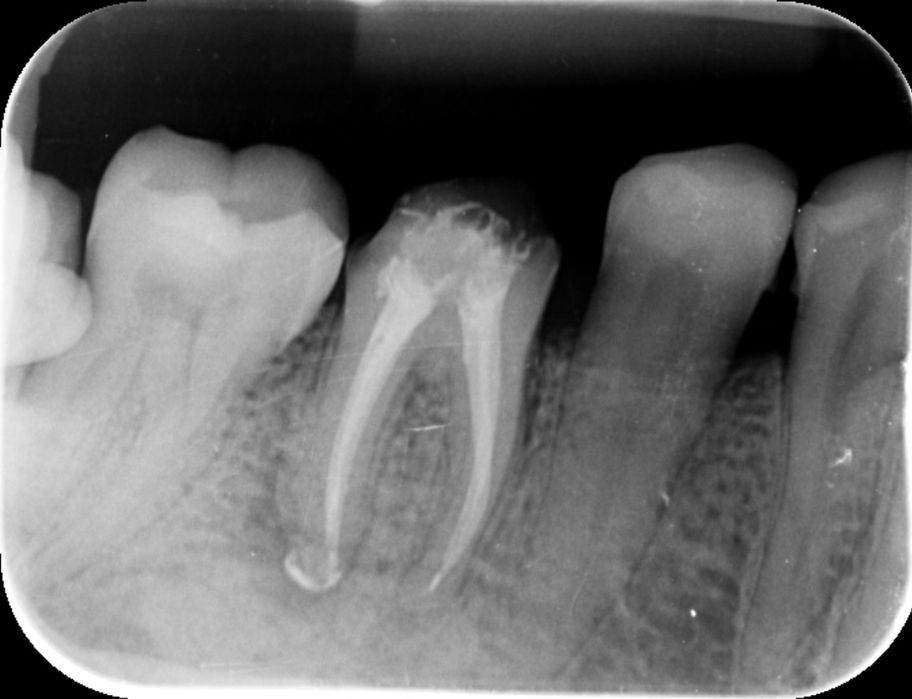

Alguns casos de sucesso